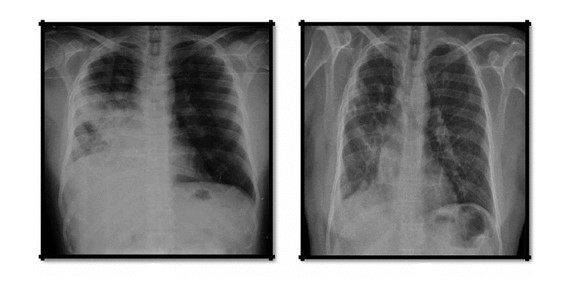

患者59岁,男性,无吸烟史,有过敏性鼻炎和支气管哮喘的病史。 2017年5月,患者做支气管镜引导活检的组织病理检查发现肺腺癌。2个月后,患者出现左侧肺炎,并用多种静脉注射抗生素治疗。同时进行纤维支气管镜检查,显示右上叶脓性分泌物和右中叶开口狭窄。患者症状恶化,支气管活检结果显示EGFR突变阴性。为了进一步诊断,进行荧光原位杂交测试,其显示ROS1突变阳性。患者开始使用印度卡布宁caprane克唑替尼250mg,每日两次治疗。一个月后患者情况好转。 2018年3月,复查结果显示患者总体上胸廓清晰,疗效良好。